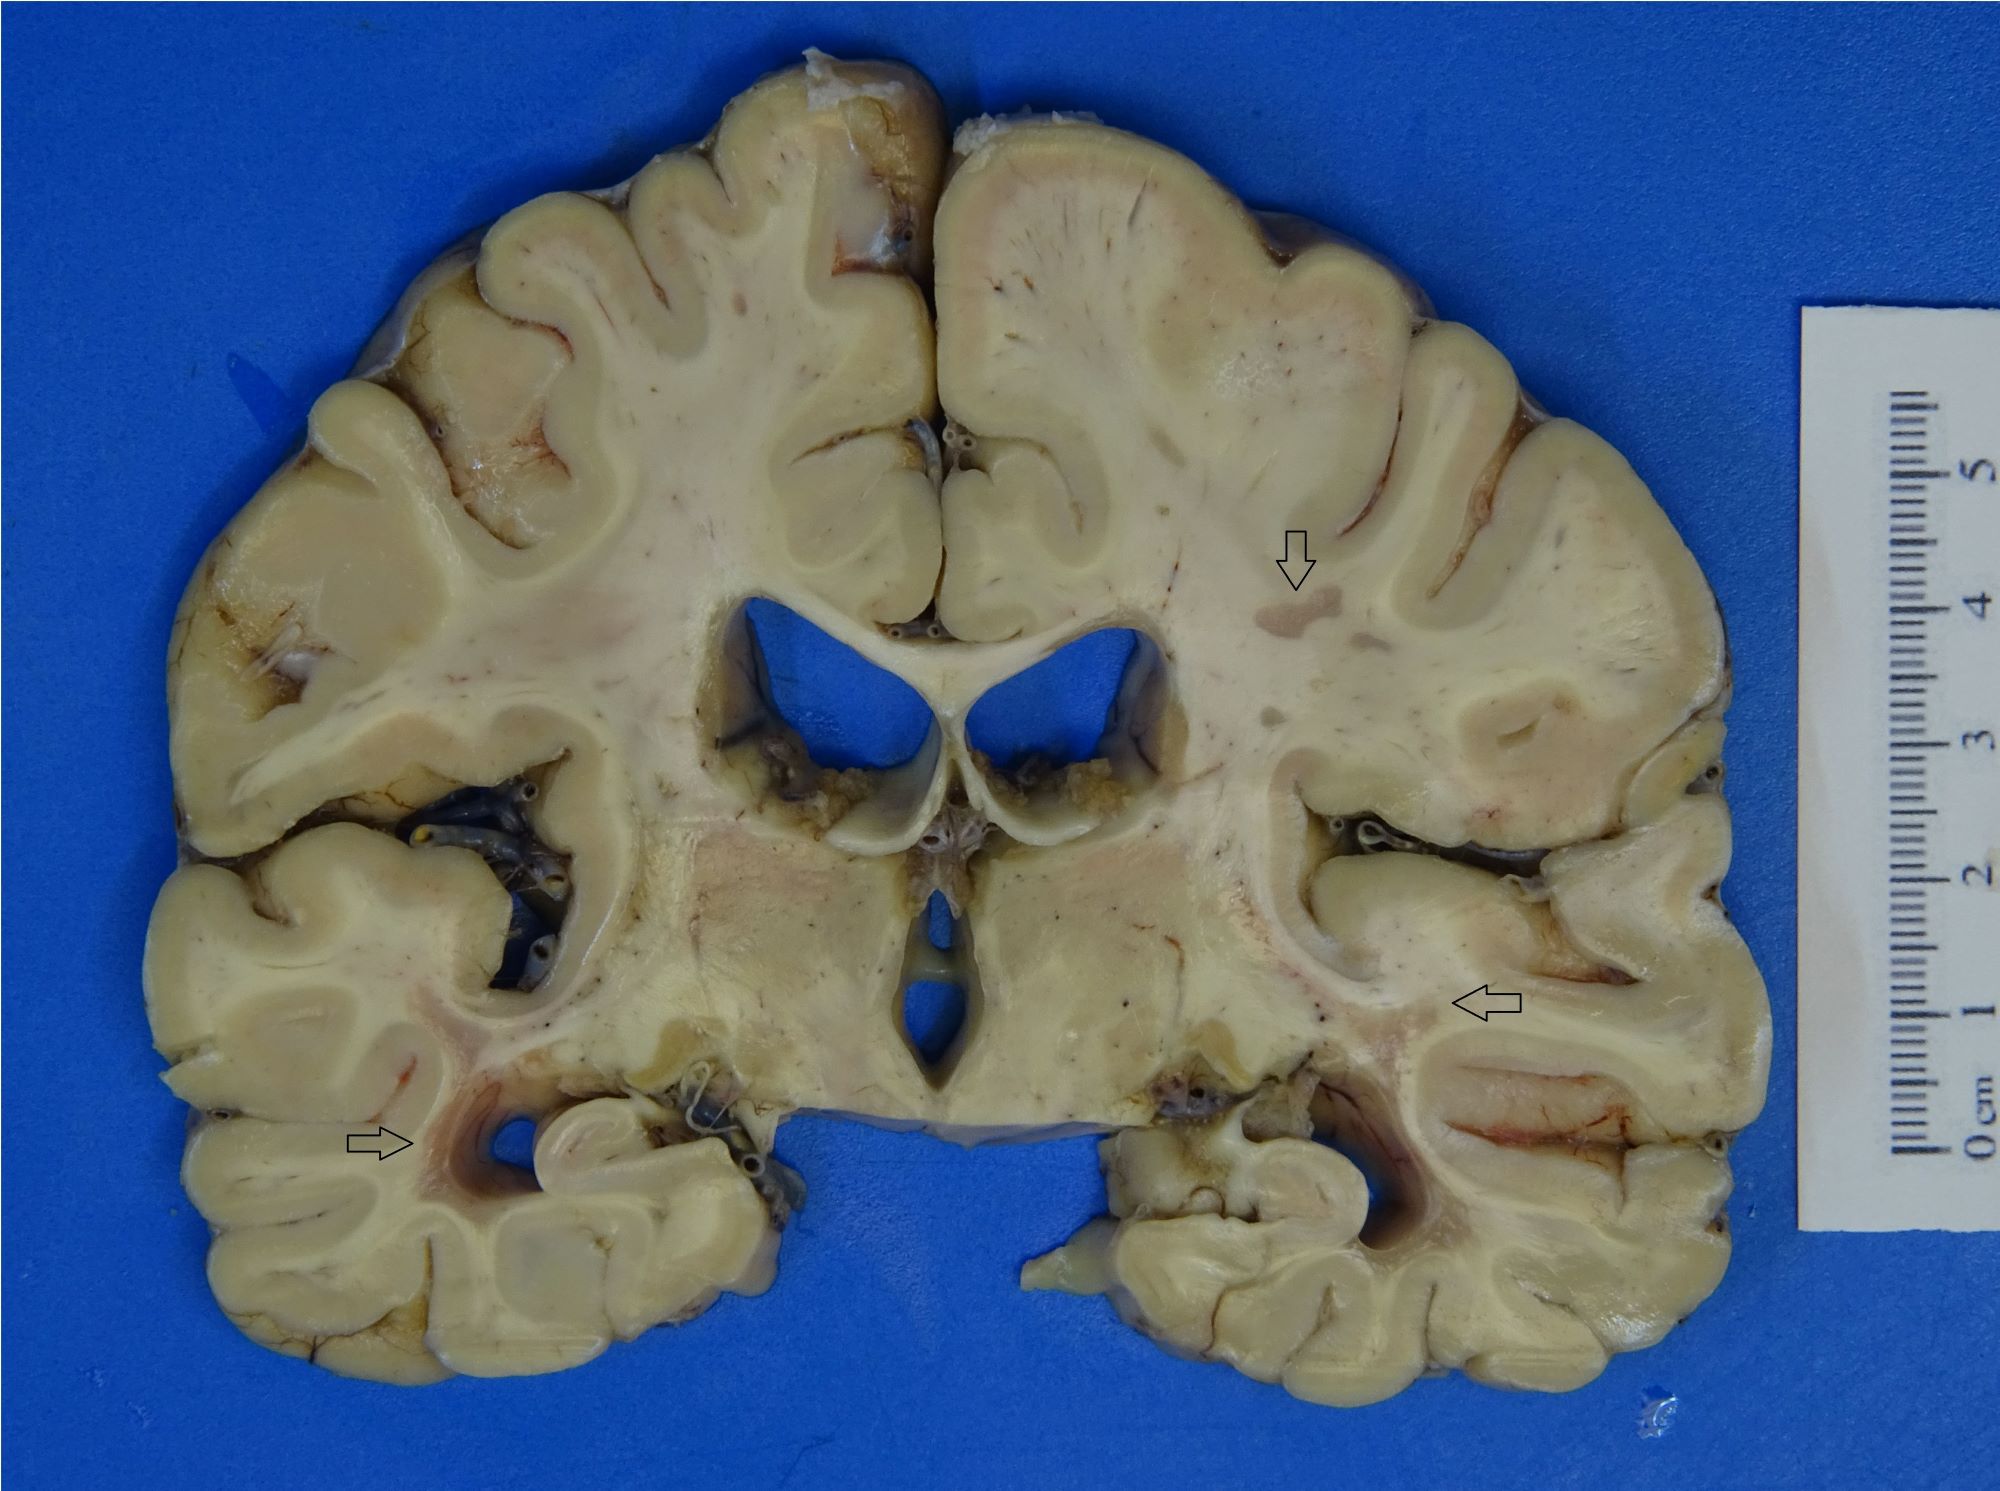

Gross description

- Chronic plaques tend to be rounded, tan-gray and variably sized with a sharp demarcation from the surrounding brain tissue

- More recent lesions will be tan-pink or tan-yellow with less sharply defined borders

- In the spinal cord, plaques will have a fanned out appearance with sharp borders and can potentially involve multiple adjacent signaling pathways (Pract Neurol 2016;16:279)

Gross images